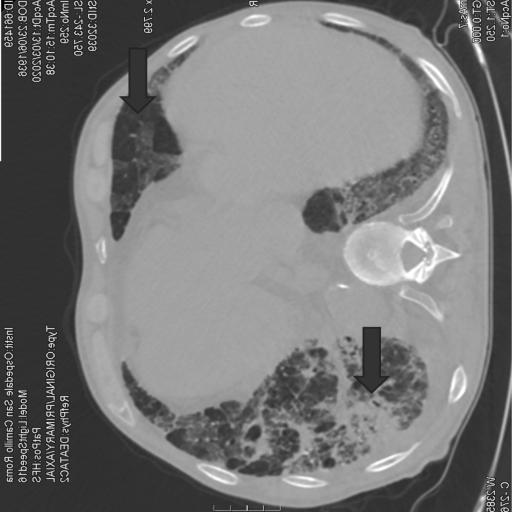

The following is an AI medical segmentation tool for detecting ground-glass, consolidation and pleural effusion in patient lung CT scans. Some reports have shown that ground-glass/consolidation measurements can further enhance the prognosis estimation for Covid-19 patients.